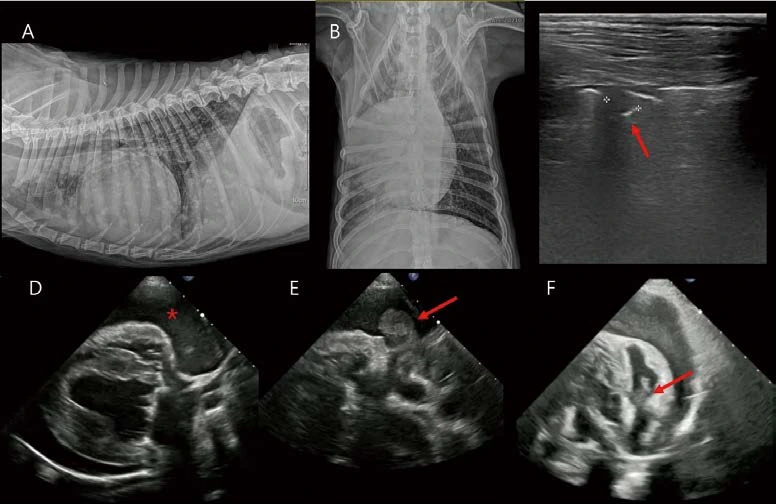

13살 수컷 26.5kg Golden retriever가 급성 기력저하로 내원하였습니다. 심한 노력성 호흡 상태에 혈압은 80mmHG였습니다. 흉부방사선 검사에서 폐야 전반에 걸친 작은 연조직 밀도 결절성 음영이 관찰됩니다(A, B). 심장은 globoid cardiomegaly with sharp contour를 보입니다(A, B). 폐초음파에서 폐전이가 고려되는 결절성 음영이 관찰됩니다(C). 심초음파에서 다량의 심낭수가 관찰되며(D, *), 이로 인한 cardiac tamponade(우심실, 우심방 collapse, CVC plethora, 소량의 복수)가 관찰됩니다. 일반적으로 스캔하는 Right parasternal four chamber long axis view, short axis view에서는 종괴 음영이 관찰되지 않으나, oblique로 right auricle을 스캔하면 right auricular wall 내외로 bulging된 결절성 종괴 음영을 찾을 수 있습니다(E, F). 이 환자는 심낭수 천자 및 세포학적 검사에서 primary cardiac hemangiosarcoma로 확인되었습니다. Hemangiosarcoma는 우심방, 우심이에서 잘 발생하는데, 심초음파에서 right auricle 병변은 놓치기가 쉽습니다. 심낭수가 있을 경우에는 스캔이 잘 되는 편이나, 심낭수가 없을 경우 right auricle 또는 left auricle 병변을 간과하기 쉬우므로 심초음파 스캔 시 주의가 필요합니다.